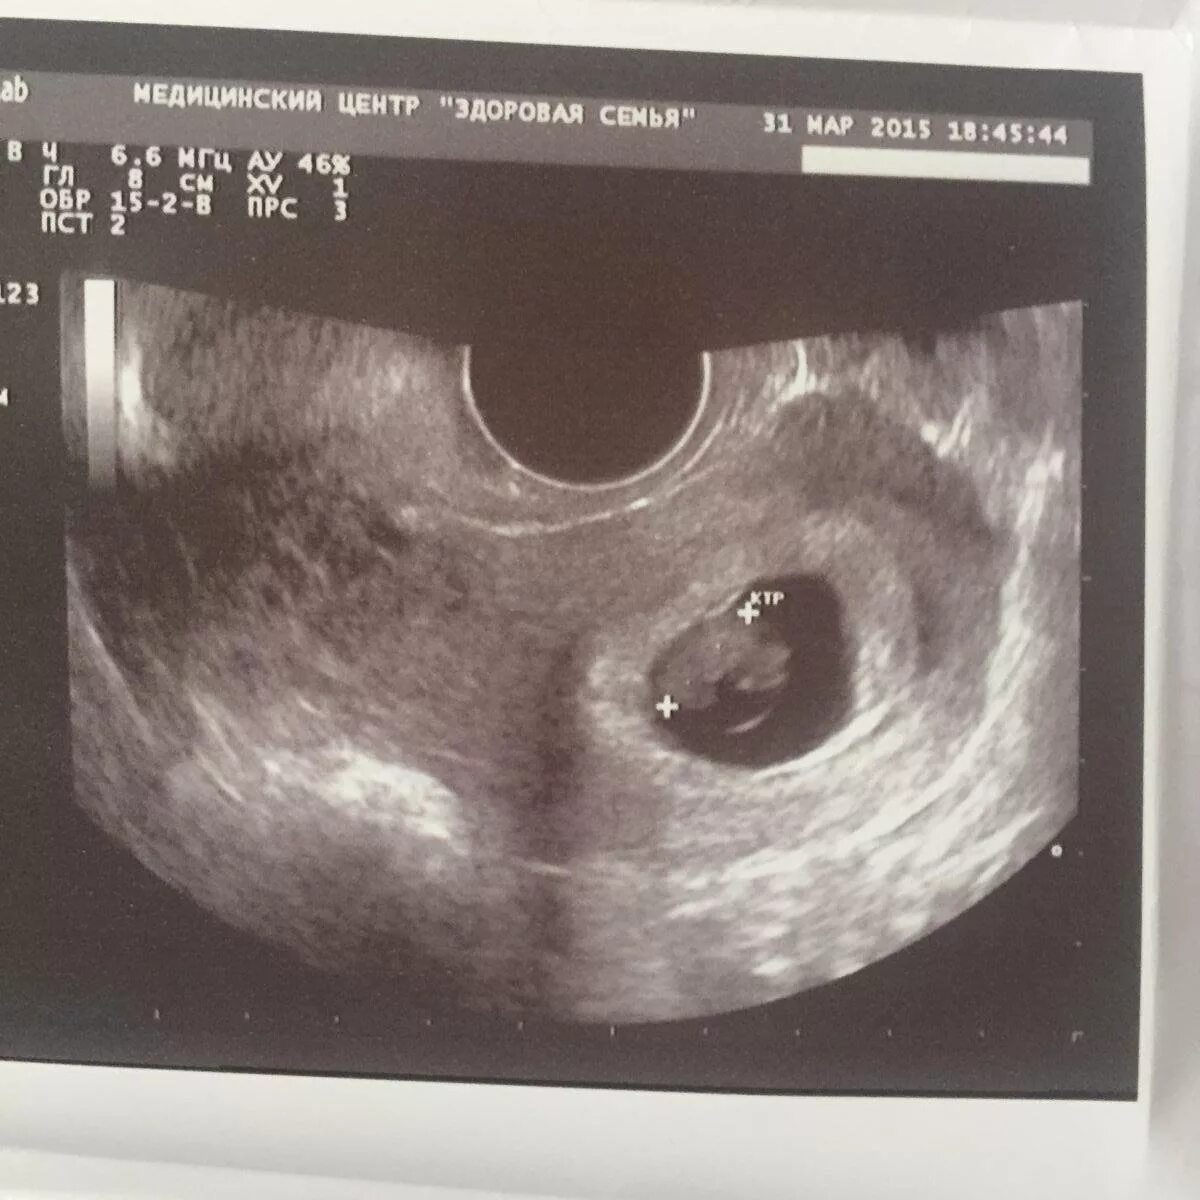

7 неделя февраля